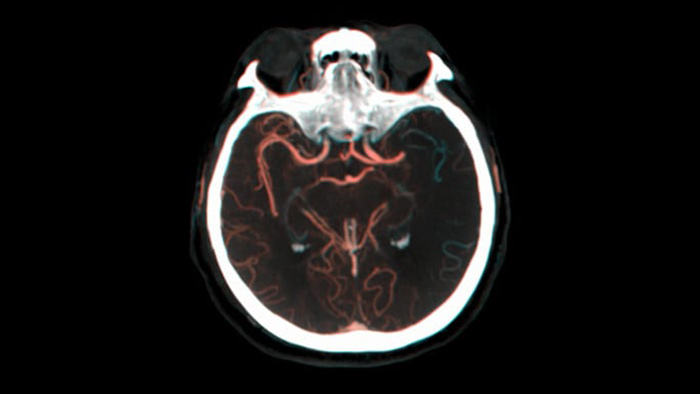

SmartCT Vaso IV

Überprüfung der Position und Länge eines Gerinnsels

Dank der periprozeduralen Darstellung von Aspekten distaler Gefäße bei ischämischen Schlaganfällen ermöglicht SmartCT Vaso den Blick hinter das Gerinnsel. SmartCT Vaso ist eine Erfassungstechnik, die auf einem Cone-Beam-CT-Scan in Kombination mit einer intraarteriellen Kontrastmittelinjektion basiert. Durch retrograde Füllung werden die Gefäßstrukturen vor und hinter dem Gerinnsel sichtbar. Die SmartCT Vaso 3D Roadmap kann zur Darstellung von Instrumenten zur Entfernung von Gerinnseln verwendet werden.

Verbesserte Darstellung des Gefäßsystems

Roadmap Pro

Treffen Sie informierte Entscheidungen, ob und wie das Gerinnsel erreicht werden kann: Roadmap Pro, eine moderne Doppelkontrast-Roadmap, verbessert die Darstellung überlappender Gefäße bei gleichzeitigem Management der Strahlenexposition.